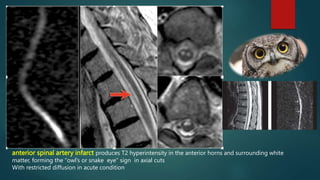

Spinal cord infarction is a rare cause of acute myelopathy, accounting for about 6% of cases of

Myelopathy

Caused include occlusion related to aortic or cardiac interventions, trauma, systemic arteriopathy

Classically, anterior spinal artery infarct produces T2 hyperintensity in the anterior horns and surrounding white

matter, forming the “owl’s or snake eye” sign in axial cuts

Posterior spinal artery infarct produces T2 hyperintensity that is limited to the dorsal columns and

posterior horns

Restricted diffusion at diffusion-weighted imaging can improve diagnostic certainty when cord infarct is suspected

anterior spinal artery infarct produces T2 hyperintensity in the anterior horns and surrounding white

With restricted diffusion in acute condition

Acute cord infarct in a 60-year-old woman after thoracoabdominal aortic

aneurysm repair.

Axial T2-weighted MR image (a), diffusion-weighted MR image (b), and apparent diffusion

coefficient (ADC) map (c) show postoperative changes in the paraspinal soft tissues (arrows in a).

There is abnormal T2 hyperintensity involving the anterior horns of the central gray matter,

demonstrating the owl’s eye sign (arrowhead in a), with a corresponding area of low SI on the ADC

map (arrowhead in b and c